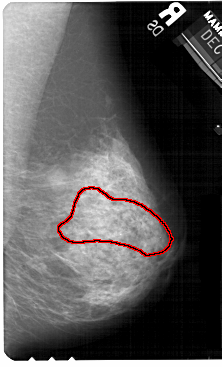

A_1511_1.LEFT_MLO

RIGHT_MLO LINES 5491 PIXELS_PER_LINE 3316 BITS_PER_PIXEL 12 RESOLUTION 43.5 OVERLAY

FILE: A_1511_1.RIGHT_MLO.OVERLAY

TOTAL_ABNORMALITIES 1

ABNORMALITY 1

LESION_TYPE CALCIFICATION TYPE AMORPHOUS DISTRIBUTION SEGMENTAL

ASSESSMENT 4

SUBTLETY 3

PATHOLOGY BENIGN

TOTAL_OUTLINES 1

BOUNDARY